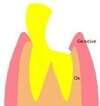

La dent a été nettoyée de sa carie et les parties fragiles ont été supprimées. Il faudra supprimer l'os et la gencive au dessus des traits noirs.

L’élongation coronaire est un repositionnement chirurgical de la gencive et une retouche du contour osseux.

La cicatrisation complète se fait en moyenne en trois mois. Pendant ce temps, la dent est protégée par une couronne provisoire.

La dent devra ensuite être reconstituée par un inlay-core et une couronne

Cette première prémolaire du haut a été détruite par la carie. Il ne reste pas suffisamment de structure dentaire pour faire tenir une couronne.

Après nettoyage et suppression des parties fragiles, on peut remarquer que la structure résiduelle dentaire est sous le niveau de la gencive.

L'élongation coronaire consiste donc à un repositionnement de la gencive, afin de dégager d'avantage la structure dentaire.

Après cicatrisation, le dentiste peut reconstituer la dent avec un inlay-core et une couronne.